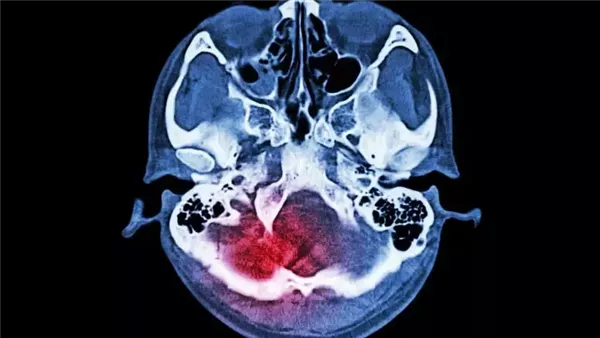

ربطت دراسة جديدة بين التدخين وارتفاع ضغط الدم والرجفان الأذيني وزيادة خطر الإصابة بالسكتات الدماغية الشديدة، وذلك وفقًا لما نشره موقع تايمز ناو نيوز.

وكشفت دراسة جديدة 3 عوامل خطر كبيرة لا تزيد من احتمال الإصابة بالسكتة الدماغية فقط، بل تزيد أيضًا من احتمالات أن تكون شديدة وتغير الحياة، إذ تشمل هذه العوامل التدخين، وارتفاع ضغط الدم، والرجفان الأذيني بالسكتات الدماغية المنهكة التي يمكن أن تجعل المرضى غير قادرين على المشي أو رعاية أنفسهم بشكل مستقل.

وحلل الباحثون بيانات من ما يقرب من 27000 شخص في 32 دولة، بمتوسط عمر 62 عامًا، ومن بين هؤلاء المشاركين، عانى نصفهم من سكتة دماغية، إذ عانى نحو 4800 منهم من سكتة دماغية شديدة و8600 منهم من سكتة دماغية خفيفة إلى متوسطة، وبعد تعديل المتغيرات الصحية الأخرى، لاحظ الباحثون أن وجود عوامل الخطر الثلاثة.